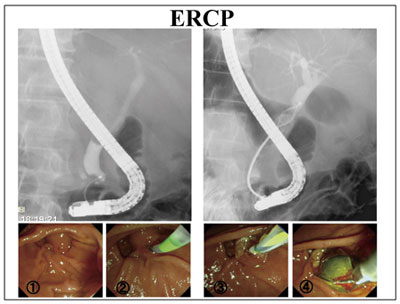

補液開始と共に、SBT/CPZ:スルペラゾ ン®2g/日投与開始したところ速やかに上腹部 痛、検査データともに改善を認めた。当院では 総胆管結石や閉塞性黄疸に対するドレナージ療 法はERCP を用いたERBD、ENBD を基本2) にしているが、本症例は、全身状態も落ち着い ており、待機的にERCP 施行した。傍乳頭憩 室症例で乳頭の固定は不良であったが総胆管造 影成功し、中部胆管に約15mm 大の総胆管結石 を疑う陰影欠損を認めた。パピロトミーナイフ にて口側隆起を超えない程度にEST(中切開)を行い、結石嵌頓も危惧されたため砕石バスケ ットで結石排石した。術中穿孔や出血は認めな かった(図9)。

図9

上段左:胆管造影で中部胆管(内視鏡裏)に陰影欠損

下段1):傍乳頭憩室 乳頭腫大

下段2):胆管挿管

上段右:砕石バスケットで結石把持

下段3): EST(中切開)

下段4):総胆管結石排石